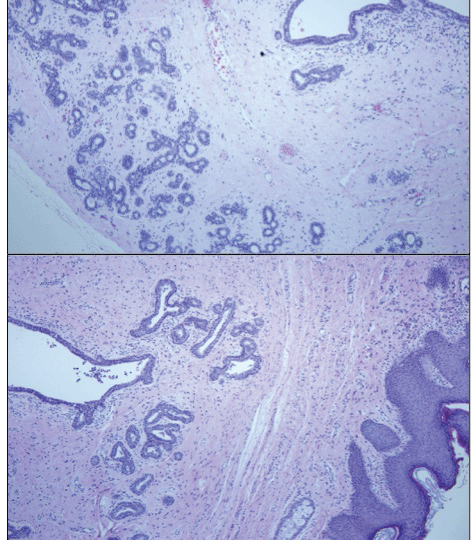

Figure 5: (Hematoxylin-eosin, original magnifications X100 [2] and X200 [1]): Histomorphological features of fibroadenoma in ectopic breast tissue: Microphotograph showing encapsulated growth consisting of compressed glands and branching ducts within a dense fibrocollagenous stroma. View Figure 5